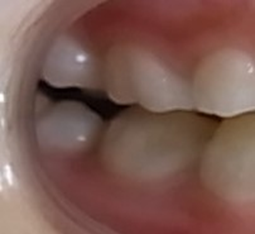

下の写真のように咬み合わせの力が弱い幼少期の反対咬合は、咬むための力を主に筋力に頼っているので治療の効果が一目瞭然に確認することができます。

不安定に見えていた咬み合わせが、反対咬合が改善されて安定して咬みあっていることが分かります。小学校低学年の治療であれば早期治療により反対咬合は容易に改善可能で、骨格の変化を考えてみても反対咬合は早期治療の効果が得られやすい症例と言えます。